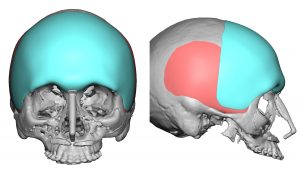

A: Thank you for your inquiry and your very articulate and intellectual description of your aesthetic head shape concerns, objectives and the aesthetic challenges that come with trying to rectify them all in a proportionate and harmonious manner. I will answer your questions in detail but have attached a few prior patient custom skull implant designs in the spirit of ‘a picture is worth a thousand words’ that have addressed similar patient concerns.

A: Thank you for your inquiry and your very articulate and intellectual description of your aesthetic head shape concerns, objectives and the aesthetic challenges that come with trying to rectify them all in a proportionate and harmonious manner. I will answer your questions in detail but have attached a few prior patient custom skull implant designs in the spirit of ‘a picture is worth a thousand words’ that have addressed similar patient concerns.

1) Any implant design that needs to go past the bony temporal line will sit on top of the temporalis fascia/muscle.

2) Depending upon how much the implant design crosses the temporal and how much forehead width and frontal augmentation is needed, the implant design may have to cover the anterior temporal region to prevent creating unaesthetic temporal hollowing.

3) In men you design as part of the implant a temporal line of transition between the forehead and the temporal area. (subtle raised ridge) In women this is not necessary.